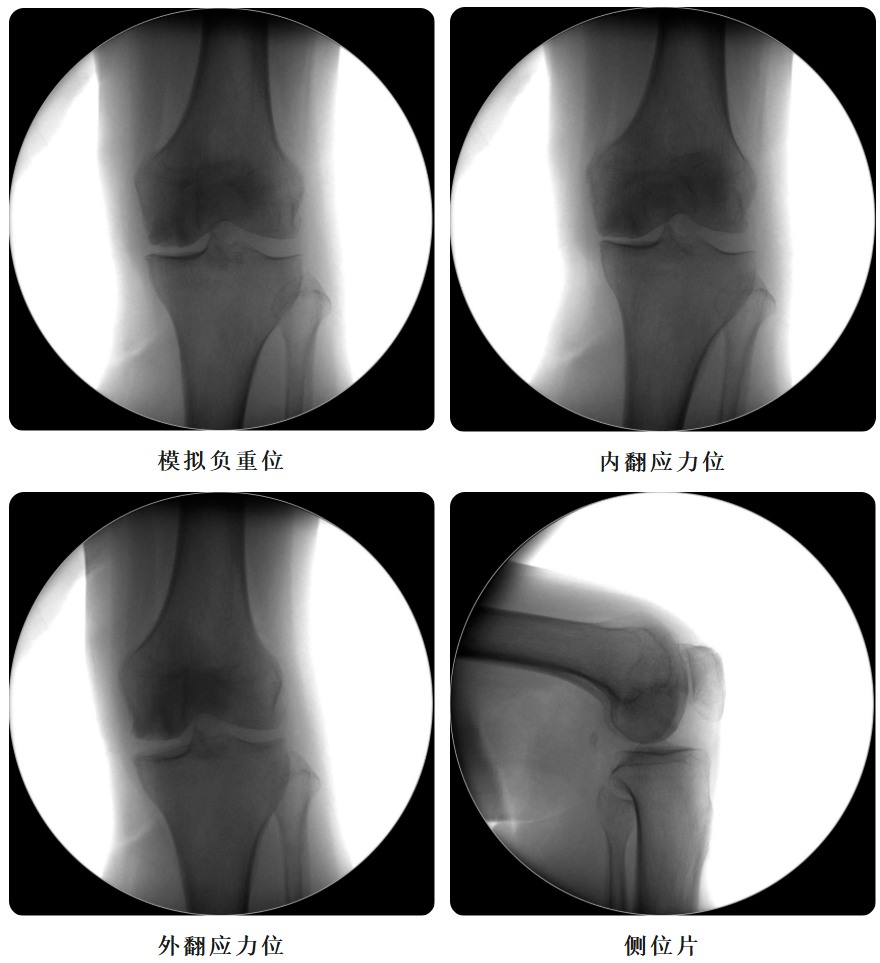

术前透视片